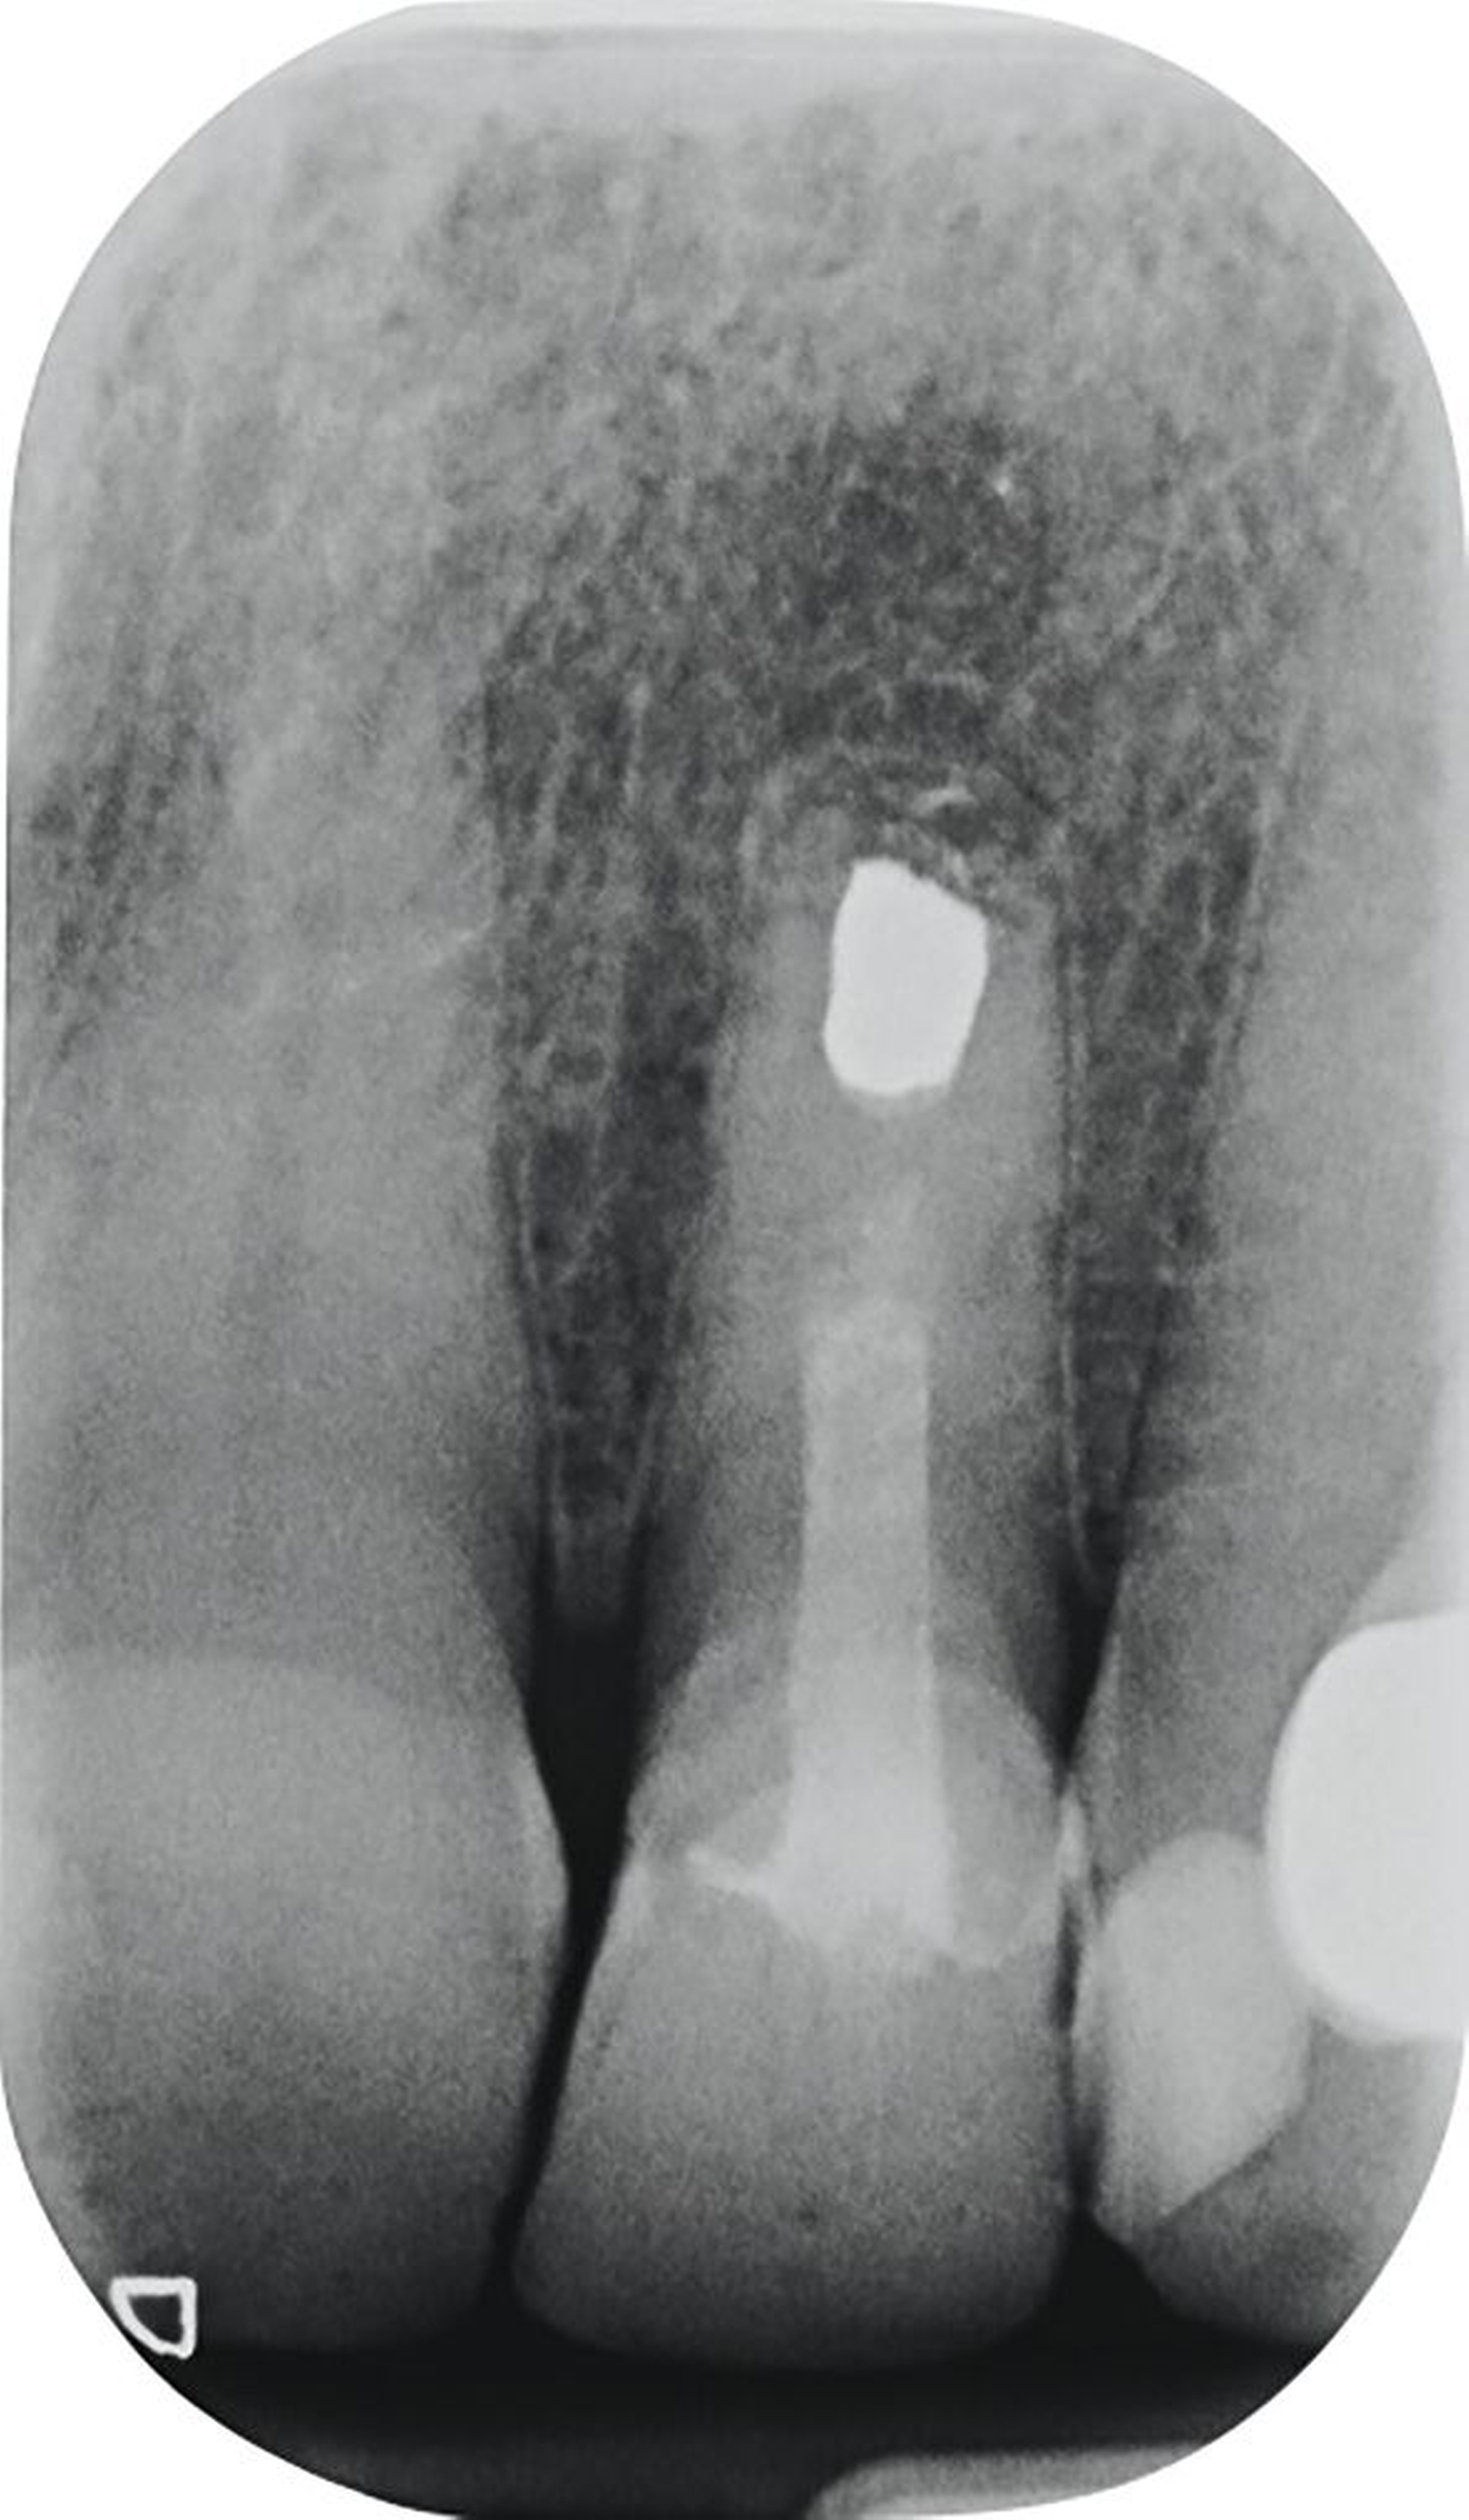

Vor 25 Jahren hatte der Patient ein Frontzahntrauma an Zahn 22 erlitten, der daraufhin mit einer Wurzelspitzenresektion und einer retrograden Amalgamfüllung versorgt worden war (Abbildung 3a). Dabei war die Zahnkrone mit einer keramisch verblendeten Stiftkrone aus Nichtedelmetall rekonstruiert worden, die nun aufgrund von Sekundärkaries insuffizient und gelockert war, jedoch keine Beschwerden verursachte. Klinisch wies der Zahn eine sehr kurze klinische Krone ohne ausreichendes Ferruledesign auf (Abbildung 5a) [Naumann et al., 2018a; Naumann et al., 2018b]. Neben dem Verdacht auf einen obliterierten mittleren Wurzelkanalabschnitt gab es röntgenologisch keinen Hinweis auf apikale Osteolysen oder parodontale Auffälligkeiten (Abbildung 3b). Der Patient entschied sich trotz des erhöhten Zahnhartsubstanzdefekts für den Zahnerhalt durch einen adhäsiv verankerten Kompositaufbau.